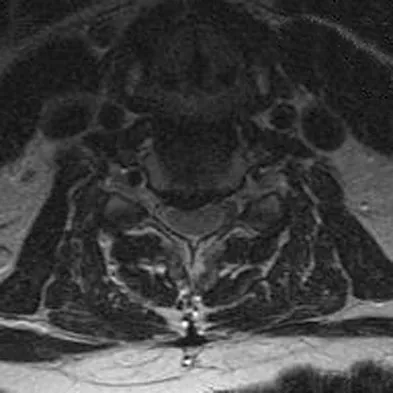

A 65-year-old man with ankylosing spondylitis has neck pain after falling back over his lawnmower, striking his thoracic spine, and forcing his neck into extension. Examination reveals subtle weakness of the intrinsics and finger flexors at approximately 4+/5. Initial management consists of immobilization in a rigid collar, and placing his head in the anatomic position. Radiographs reveal a subtle extension fracture of the lower cervical spine. Approximately 6 hours after the injury, he reports increasing paresthesias in his upper and lower extremities, and examination now shows his intrinsics are 2/5, finger flexors are 3/5, and his triceps are now weak at 4/5 on manual motor testing. In addition, his lower extremities now show weakness in both dorsal and plantar flexion of the ankle in the range of 4/5. Repeat radiographs appear unchanged. An MRI scan is shown in Figure 2. Management should now consist of

Explanation

It is not uncommon for patients with ankylosing spondylitis to sustain extension-type fractures, most typically of the cervicothoracic junction. These fractures can appear nondisplaced or minimally displaced initially, making them difficult to diagnose. Because there is no mobility between vertebrae, fractures tend to occur more like those of a transverse fracture of a long bone. In addition, the vertebral bodies are vascular and their canals are relatively enclosed, making them vulnerable to epidural bleeding. The MRI scan reveals an epidural hematoma located posteriorly on the cord; therefore, the treatment of choice is surgical evacuation and a posterior laminectomy. Because of the intrinsic instability of such fractures at the time of the laminectomy, internal fixation and stabilization with a posterior fusion is warranted. A simple laminectomy will only increase instability, and control is unlikely with halo vest immobilization. An anterior procedure will not effectively treat the problem given the location of the hematoma. Consideration can be given to methylprednisolone and observation; however, this will not eradicate the problem. Bohlman HH: Acute fractures and dislocations of the cervical spine. J Bone Joint Surg Am 1979;61:1119-1142.